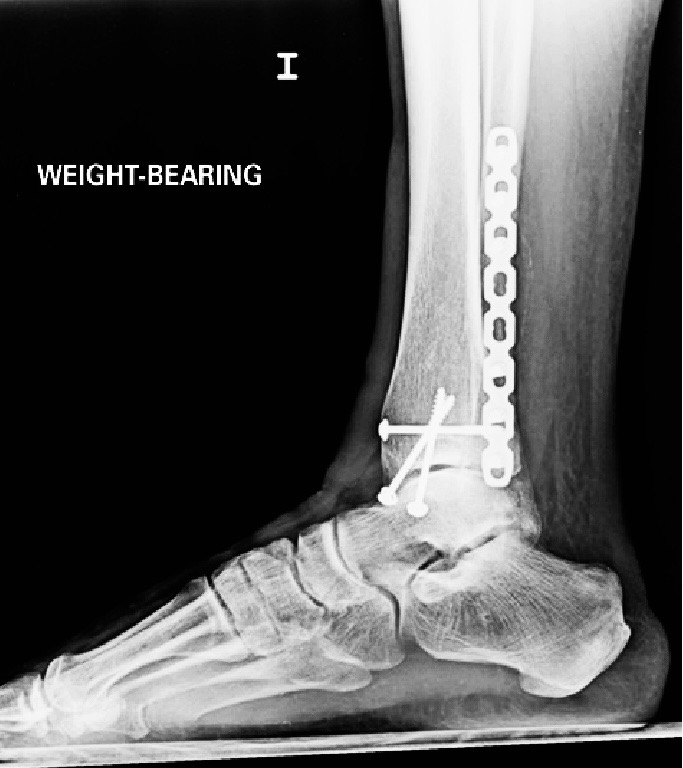

Two weeks ago, I underwent surgery to begin the healing process on a trimalleolar ankle fracture. (which by the way i don’t recommend this kind of fracture at all!) While I’m incredibly grateful the procedure went well, recovery has been tough — physically, mentally, emotionally, and financially. I’m doing my best to stay strong, but the truth is, this situation has left me in a really difficult place.